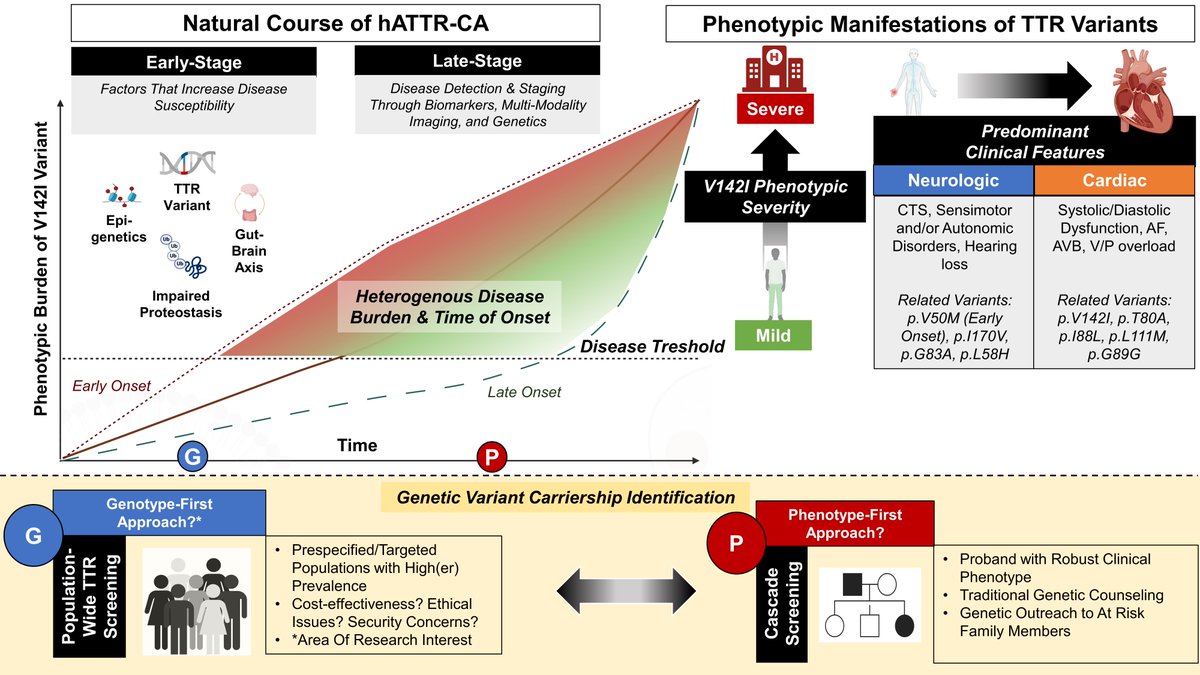

Genotype-phenotype interdependence in hereditary ATTR-CA with p.V142I variant Justin L. Grodin Silvio Augusto Jr. W. H. Wilson Tang, MD Simon Vanhentenrijk #AHAJournals ahajrnls.org/3GdCQ7e